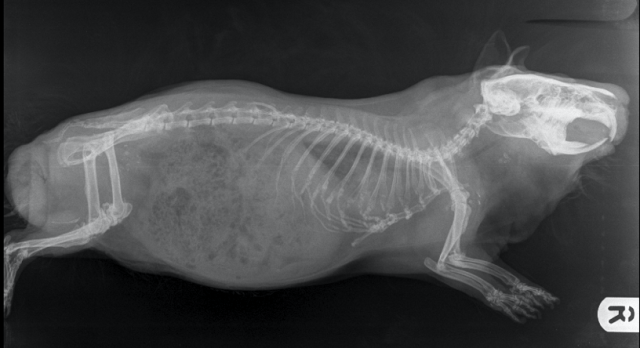

We showed you Neville’s x-rays on the A to Z in 2022; you can see those here in detail, especially at the top of the page — it’s easy to see his round bladder stones between his hip and his spine (high up in his bladder).

It’s not easy to see those floating rib cartilages in this view, but you can tell they don’t join up below. And if you compare it with Neville’s you might see why.

If you follow Neville’s breast bone down, it ends in a bone which takes the line of the others. Now look at mine. It points down!